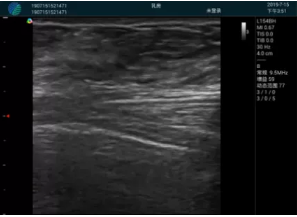

可視化甲狀腺穿刺引導(dǎo)

頸動脈血流充盈飽滿,無外溢

肝內(nèi)血管顯示清晰,血流敏感無外溢